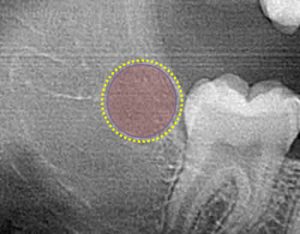

Zero3 technology has built-in controls to assure that the 3TBA procedure results in gently warming the targeted tooth bud (circled) from the center outwards to reduce the risk of adversely effecting adjacent tissue while clinically inducing 100% molar agenesis.

Zero3 technology controls the 20-40 second ablation process to gently warm the targeted tooth bud tissue (circled) from the center outwards to clinically induce prescribed molar agenesis while not significantly effecting adjacent tissues.